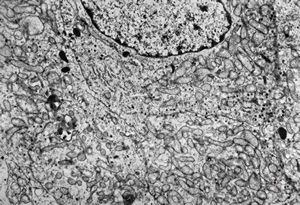

M, 63y. | suprarenal neuroblastoma